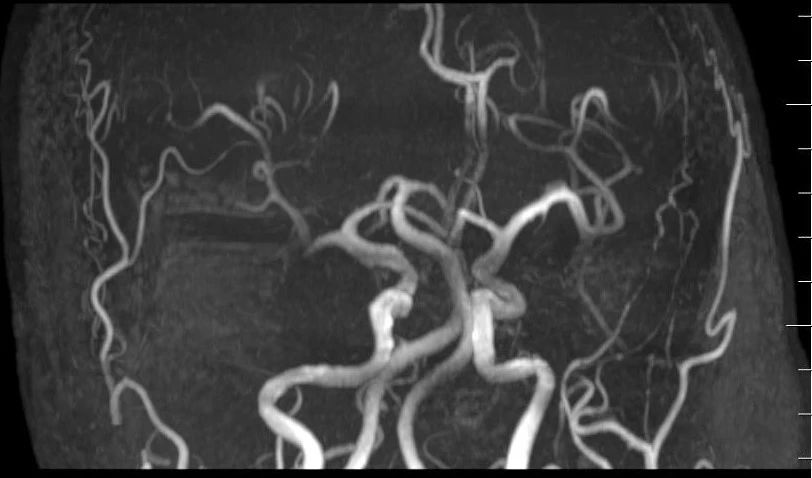

高场强设备(如3.0T MRI)提供更高分辨率的图像,能清晰显示血管狭窄、动脉瘤(≥3mm)、血管畸形等病变。研究显示,其对缺血性脑血管病的诊断灵敏度达95.2%,优于低剂量CTA。

一次检查可同时观察头颈部动脉主干及分支,结合平扫还能评估周围脑组织是否受损(如缺血灶),适合筛查脑卒中或复杂血管病变。